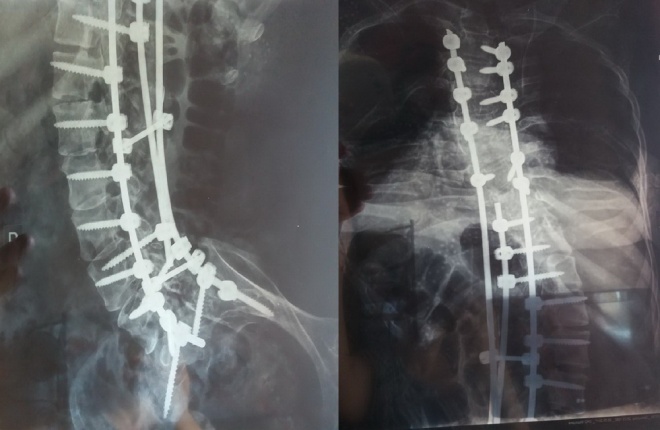

Семнадцатого мая мне была сделана операция, а первого июня меня выписали.

Операция длилась 8 часов, вытянули меня очень сильно,примерно стала выше на голову.

Теперь сижу ровно, не заваливаюсь. самостоятельно держу баланс, дышать легче, даже разговаривать легче, стало возможным крутить колеса ручной коляски. Очень сильно поменялся мой внешний вид.

Сейчас я дома, учусь жить по новому, приспосабливаться к быту, это не скрою, очень трудно, когда, ты 30 лет прожил в скрюченном положении и привык все так делать. Старая коляска мне теперь не подходит,у нее оказалась короткая спинка для моей новой спины (сорри за каламбур). Нужен подъемник, нужно тренировать легкие, нужна реабилитация. Но самое главное, что сама операция прошла успешно.

Это чудо, что у нас есть такой врач от Бога, как Андрей Николаевич Бакланов и его команда. Чудо, что мне повезло с Вашим фондом и добрые люди помогли собрать деньги на импланты. Я не представляю, что простые люди делали бы без вас!